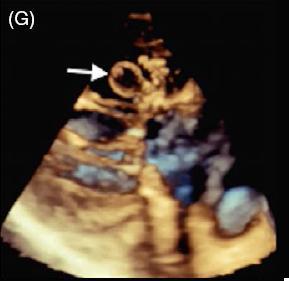

患者女,42 岁,以「急性视网膜动脉闭塞」病史就诊,既往无慢性疾病。经胸超声心动图检查发现二尖瓣后叶可见一囊状结构,可活动(图 A 和 B)。二维和实时三维经食管超声心动图检查显示一柔软的圆形结构附着于二尖瓣后叶,活动性良好(图 C ~ G)。主动脉弓、左心房、左心耳和左心室均正常。根据病变形态特征及超声表现,诊断为二尖瓣附瓣。其它影像学检查如 MRI、颈动脉多普勒超声均无异常。基于上述检查结果,考虑急性视网膜动脉闭塞为 AMVT 所致,建议外科手术切除二尖瓣附属组织,但是患者拒绝,选择随访观察。

图 G 实时三维经食管超声心动图显示一柔软的圆形结构附着于二尖瓣后叶,活动性良好